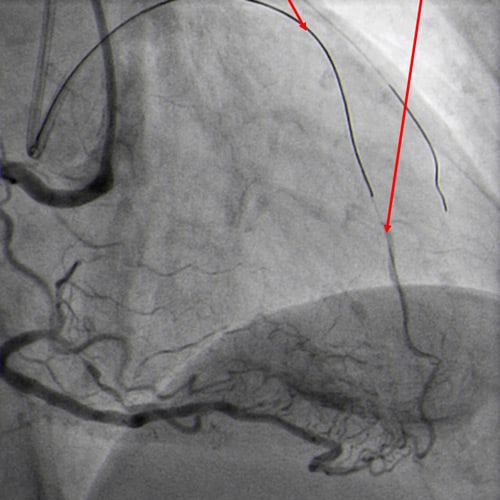

Double radial access with guiding catheter 6F JR 4.0 and sheatless 7.5F PB 3.5. Controlateral injection to check antegrade wire position via collaterals (Figure 4.1).

Antegrade guide wire position (Figure 4.1)

CTO crossed with Miracle 6g, after unsuccessful attempts with Sion and Pilot 150. Floppy wire in diagonal branch to improve support (Figure 4.2).

Guide wires to LAD and diagonal branch (Figure 4.2)